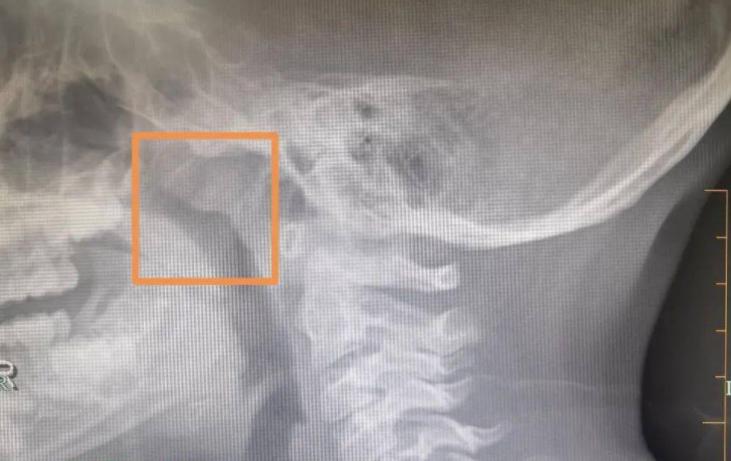

耳朵問題的「時間跨度」尤其關鍵。如果你發現自己耳鳴超過兩周,或者耳後腫塊超過一個月不消,即使沒有其他症狀,也該去檢查。不是去挖耳朵,而是做一個鼻咽、頸部的影像學檢查,可能更有意義。